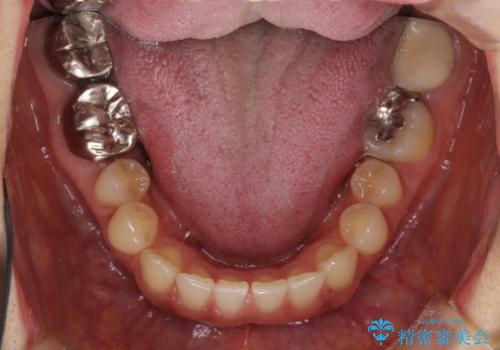

隙間だらけの歯列をきれいに インビザライン矯正とセラミック補綴治療

- 前歯の隙間と奥歯の目立つ銀歯を気にして来院された患者様です。

インビザラインにより下顎前歯の隙間を閉じるとともに、奥歯の咬み合わせを改善させることとしました。

矯正治療後には、銀歯のクラウンをセラミッククラウンへ替える補綴治療を行うこととしました。

左右奥歯の咬み合わせを変更させる必要があったため、治療期間は長くなることが予想されました。

1日22時間以上の装着時間をしっかりと守ってくださったので、順調に治療を進めることができました。